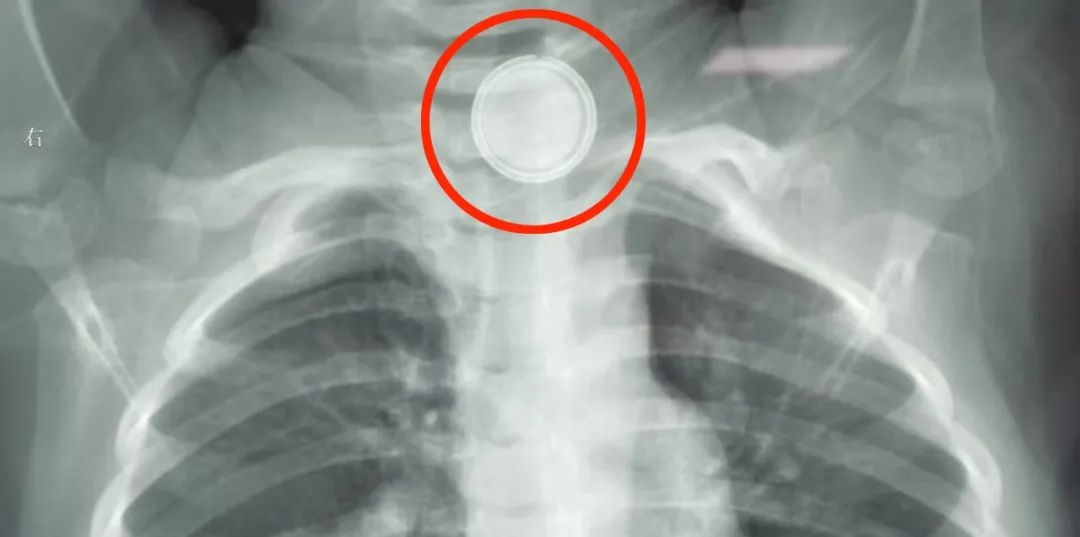

小敏病情加剧,家长迅速将她送回医院。通过胸部X光检查,发现令人震惊的情况——食道第一狭窄部位,即胸骨上方,竟然有纽扣电池堵塞。鉴于当地医疗资源有限,家长毫不犹豫,立即将小敏紧急送往北京儿童医院集团旗下的长春市儿童医院。